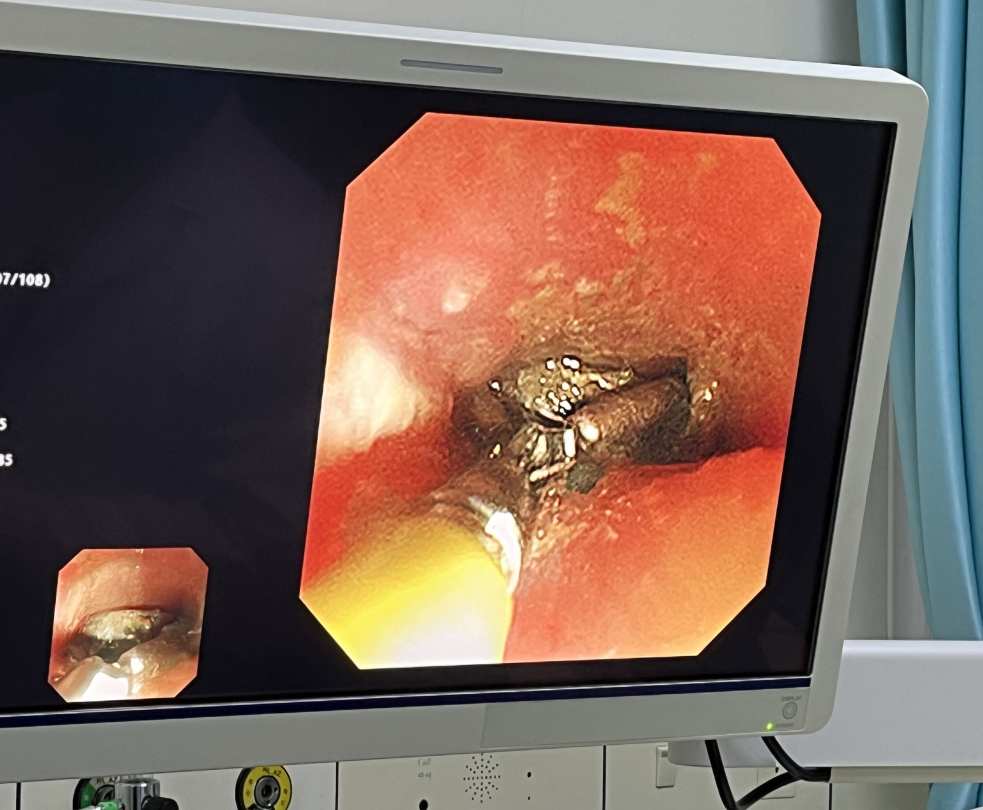

警报虽然解除,但术中发现患儿食管粘膜后壁侧发黑、质脆,取出后可见患儿食管上段距门齿约12-16cm处后壁大范围电灼伤。郝医生考虑到,可能由于患儿呕吐导致电池短路引起食管损伤,可能出现感染、食管穿孔、水肿压迫气管影响呼吸、出血、食管气管漏等近期并发症,可能出现食管狭窄、吞咽困难等远期并发症。给予留置胃管,少量多次喂养,嘱咐患儿头高脚低体位,避免返流对症治疗。

2023年3月2日,为了解患儿恢复情况,儿内二科再次联合麻醉科采用无痛电子胃镜观察患儿食管壁情况,患儿食管壁恢复良好,办理出院。患者家属万分感激,专程来到儿内二科赠予一面锦旗